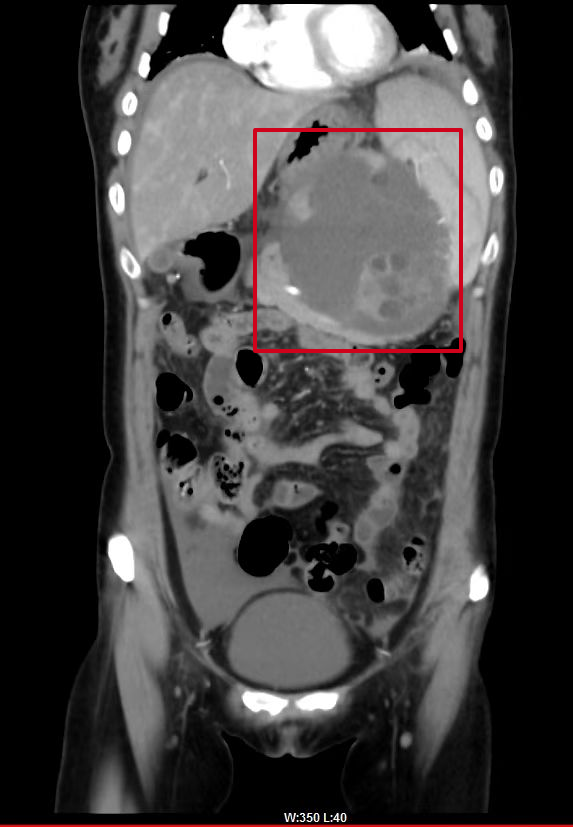

術後(hòu)複查CT提示:

巨大腫瘤已被(bèi)切除